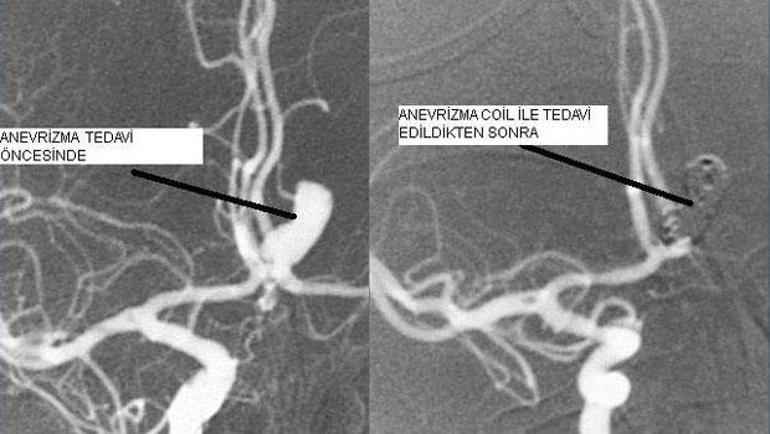

Sak geçiren hastaların 10 15 i hastaneye ulaşmadan ex olur. Bu nedenle en iyi tedavi seçeneği oldukça kişiselleştirilmiş kalır. Dedemin anjiyosunu sorunsuz şekilde gerçekleştirdi dedem çok hasta olmasına ra ğmen hastaya gereksiz islemde bulunmuyor hastayı hasta yakınlarını muhakkak anlayici bir dilde ifâde ediyor. Işini de en iyi şekilde yapıyor.